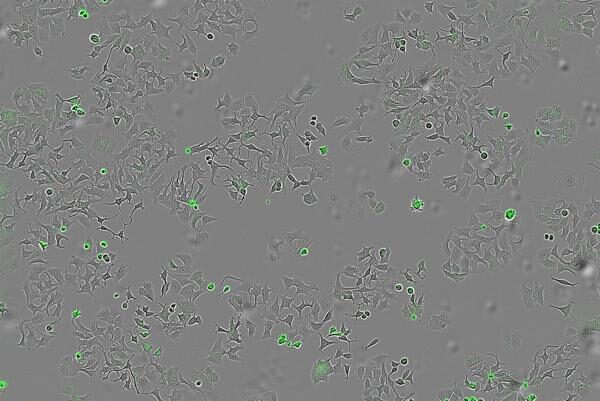

En la investigación han empleado sistemas avanzados de imagen en tiempo real que permiten contar células vivas y muertas, y medir la apoptosis (muerte programada) para observar con precisión el bloqueo de las vías.

Para desarrollar este estudio se cultivó la bacteria ‘vibrio cholerae’, contando con una cepa normal y otra mutante modificada genéticamente, y posteriormente se recogió ‘supernatante’, que es el líquido donde crecen estas bacterias y que también contiene las proteínas y sustancias liberadas por la bacteria, y se aplicó a células cancerosas humanas de colon, mama y páncreas para observar qué efectos producía.

El equipo científico empleó tanto el cultivo bacteriano original como bacterias inocuas artificialmente modificadas para producir solo HapA, y así se demostró que el efecto era realmente causado por esta proteína concreta y no por otros posibles factores de la bacteria.